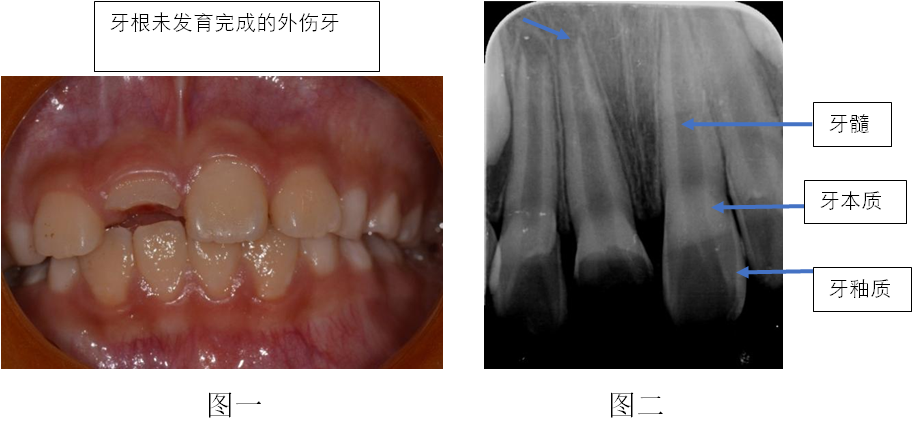

年轻恒牙是指牙根尚未完全发育形成的正在生长发育中的恒牙,在形态和结构上均未完全形成。正常情况下,刚萌出的恒牙其牙根形成大约为2/3,萌出后牙根会继续发育,3~5年后才能完成发育。

我们故事中的小主人公受伤的牙齿就是年轻恒牙,牙根并没有发育完成,如下图。如果放任不管,牙宝宝有可能不能如愿长成大牙!

牙齿磕掉一块,磕了多大的一块,差别可大不一样!首先要知道牙齿的结构,牙齿硬组织分两层,外层釉质,里层牙本质,牙本质是与牙髓(老百姓通常所说的牙神经)相通的。牙髓对于儿童牙齿来说是重要的,功能就是维持牙根的继续发育。牙本质上有我们肉眼看不到的小管道,在年轻恒牙特别粗大,内外交通特别明显,如果有不良刺激,吃的东西有细菌,冷热刺激时间长等,感染可以累及牙髓,都可能导致牙髓发炎。牙髓露出来就更不用说了!